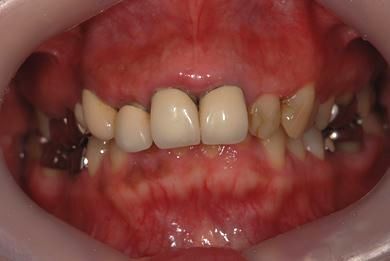

| 性別/年齢 | 女性 / 41歳 | ||||||||||||||||||||||||||||||||

| 主訴 | 歯が欠けたので、セラミック治療をお願いしたい。 | ||||||||||||||||||||||||||||||||

| 治療方針 | セラミック治療にて、審美的回復を行う。 | ||||||||||||||||||||||||||||||||

| 治療内容 | エンプレスオールセラミッククラウン4本(オールセラミック用土台4本) | ||||||||||||||||||||||||||||||||

| 総治療費 | 408,000円 | ||||||||||||||||||||||||||||||||

| 治療期間 | 4ヶ月 |